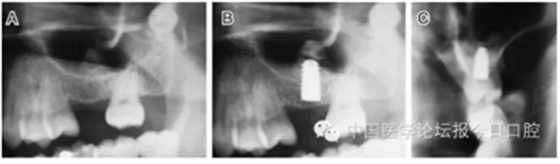

臨床上,可使用曲面體層放射線法及CT掃描方法對上額竇及可用骨量進(jìn)行評估。其中曲面體層放射線法可提供多數(shù)病例的硬腭致密影像,為治療計(jì)劃提供有價(jià)值的參考(圖1);而使用CT掃描可提供骨密度信息。如骨高度、密度、牙槽嵴的方向位置,皮質(zhì)骨和松質(zhì)骨的特點(diǎn),上頜竇黏膜厚度,病理狀態(tài)等。顯然,在上頜竇底提升術(shù)中,CT掃描影像的信息對于手術(shù)設(shè)計(jì)和減少治療風(fēng)險(xiǎn)非常重要。

圖1 采用曲面體層放射線法評估